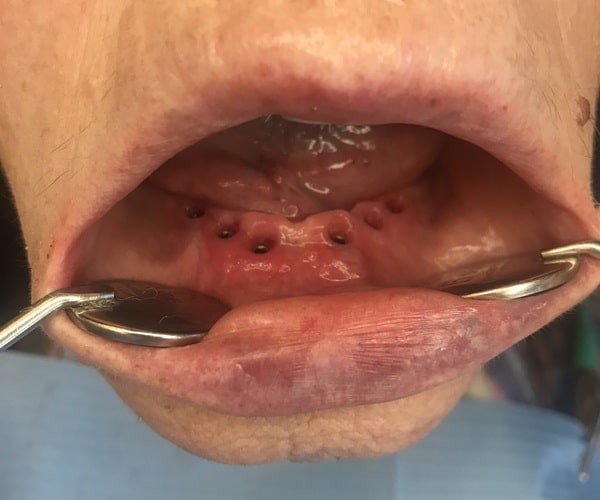

Εμφυτευμάτων Δοντιών – Πριν & Μετά